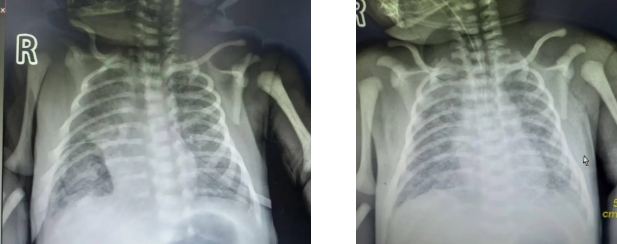

患儿因“羊水Ⅲ°浊、窒息复苏后呻吟、呼吸费力”入院。出生时Apgar评分1分钟7分,出生后出现严重呼吸窘迫及低氧血症,入院后的血气分析提示存在严重低氧血症和二氧化碳潴留,重度呼吸性酸中毒。胸片显示双肺斑片状阴影,符合重度MAS。此病例病情危重,进展迅速,救治难度大,给我院新生儿科带来了严峻的挑战。

入院第二天,患儿心彩超提示:中度肺动脉高压(PASP 56mmHg),诊断为PPHN。团队立即启动NO吸入治疗(20ppm),显著降低肺血管阻力,改善氧合,避免了ECMO的使用,体现了NO在PPHN救治中的关键作用。